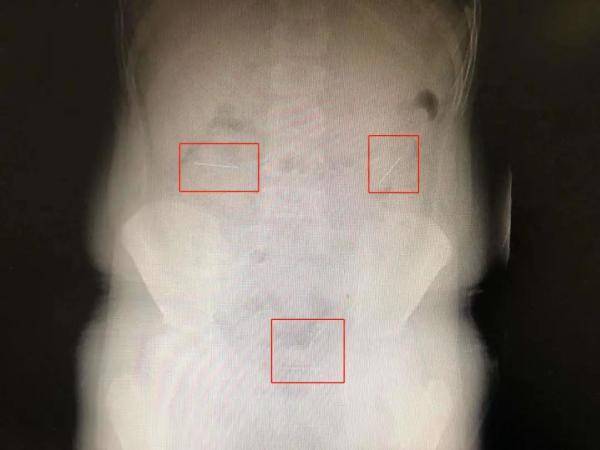

妈妈赶紧带他到医院 。 经胸片等检查 , 乐乐的左上腹有四枚针状致密影 , 正是吞下去的四枚圆头定位针——塑料圆头的铁质针 。

11月3日 , 澎湃新闻从浙江大学医学院附属儿童医院了解到 , 乐乐从当地医院转诊来时 , 通过胃镜和胸片检查显示 , 体内的4枚针已经顺着消化道进入了小肠 , 随着小肠的蠕动正往大肠方向移动 。

“我们遇到过类似的病人由于针卡在回盲部(大肠和小肠交界位置)无法排出 , 最后不得不行手术的病例 , 但看到这个孩子的定位针头上有个小珠子 , 肠道蠕动时针的方向可能会调转 , 圆头朝下随着大便自行排出的可能性还是存在的 。 ”浙大儿院普外科高志刚主任表示 , 考虑到乐乐没有腹膜炎、肠穿孔等症状 , 决定先保守治疗 , 同时做好应急预案 。 住院期间 , 高志刚建议乐乐多吃韭菜促进肠胃蠕动 , 有助于包裹定位针排出 。 等到第五天 , 四枚针都自行排出 , “最好的结局” 。